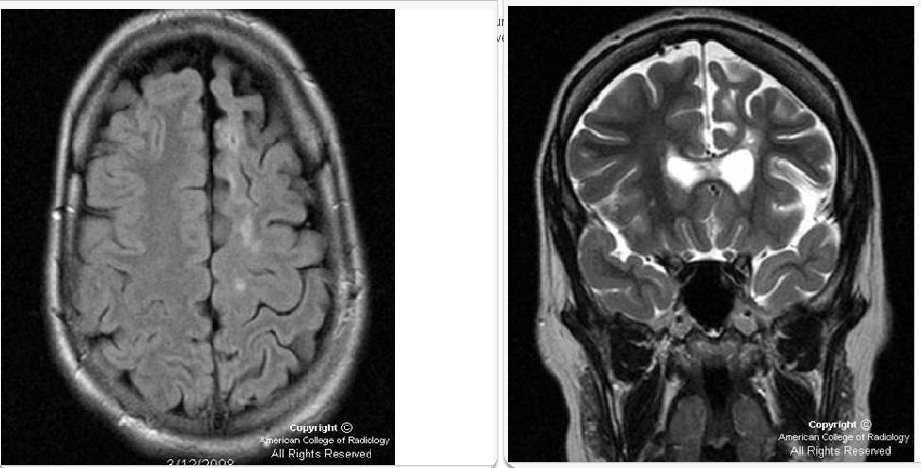

Seorang anak berusia lima tahun dengan tangan dominan sebelah kanan dinyatakan telah memiliki epilepsi sejak 4 tahun dan sering mengalami kejang motorik fokal yang persisten. Hasil pemeriksaan menunjukkan adanya gangguan perkembangan, perburukan IQ verbal dan hemiparesis sebelah kanan. EEG dan SPECT menunjukkan beberapa fokus epileptogenik pada lobus parietal kiri. Hasil MRI terlampir. Selain monitoring secara invasif, manakah dibawah ini pilihan terapi pembedahan yang paling mungkin :

B. Functional hemispherectomy

Rasmussen’s encephalitis is a rare syndrome manifested by intractable epilepsy, hemiplegia, and cognitive decline; left untreated it frequently also leads to loss of language development in young children. Epilepsia partialis continua is also a frequent feature. Imaging demonstrates diffuse hemispheric atrophy; histology demonstrates perivascular T-cell lymphocytic infiltrates. Given the inexorable decline if seizure control is not obtained, functional disconnection is indicated to also preserve language function and cognitive development. Hemispheric disconnection surgery is associated with a 70-80% success of seizure freedom in most series.